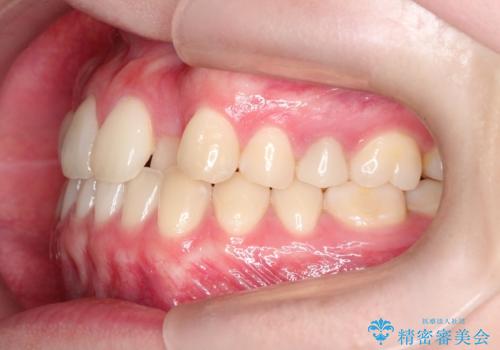

インビザラインとワイヤー矯正の併用で綺麗な歯並びに!

- 前歯のガタツキが気になるとのことで来院されました。

ワイヤー矯正とインビザライン矯正を併用することによって、治療期間の短縮と、より良い仕上がりを目指す治療を選択することとしました。

インビザライン(アライナー)矯正とワイヤー矯正のそれぞれの利点を生かした治療を行い、綺麗な歯並びになりました。